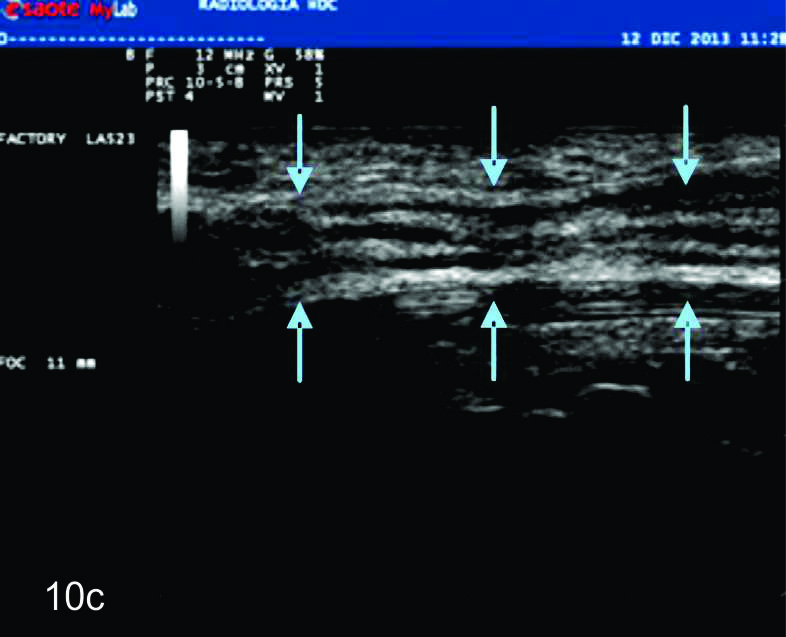

VARIANTES ANATÓMICAS Y VARIANTES DEL DESARROLLO HEREDADAS

Dada las características ultrasonográficas normales de los nervios, algunas variantes anatómicas pueden ser reconocidas por este método. Entre ellas la bifurcación proximal del mediano en el puño es una de las más frecuentes. De manera similar algunas anomalías heredables y del desarrollo del sistema nervioso periférico, como el agrandamiento fusiforme del nervio mediano por tejido fibroadiposo (denominado hamartoma fibrolipomatoso (Fig.10), la hipertrofia de los nervios en el síndrome de Charcot-Marie-Tooth y el aumento de los nervios en la neuropatía hereditaria secundaria a parálisis por compresiones pueden ser reconocidas por ultrasonido. En estas enfermedades, los hallazgos ultrasonográficos pueden contribuir a la comprensión de la fisiopatología demostrando de forma no invasiva algunos hallazgos morfológicos de interés (1).

Figura 10

Hamartoma fibrolipomatoso del nervio mediano

A y B, cortes transversales en antebrazo y puño, las flechas azules señalan al nervio mediano aumentado de tamaño con fascículos engrosados. C- Corte longitudinal con hallazgos similares en plano longitudinal del nervio (flechas azules).